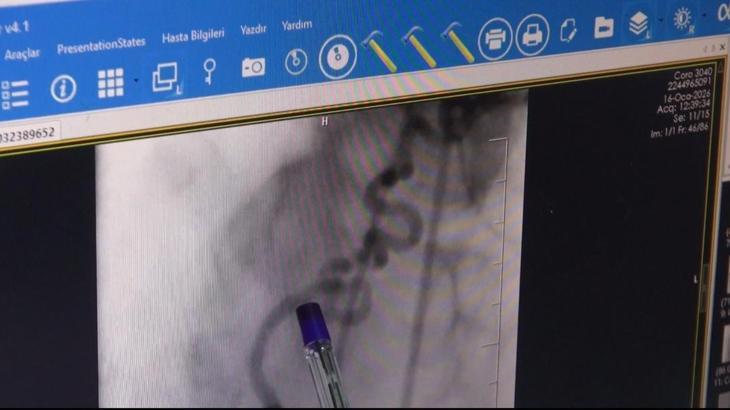

Batman’da yaşayan Şükrü Demirtaş, göğsünde yanma ve nefes darlığı şikayetiyle Batman Eğitim ve Araştırma Hastanesi Kardiyoloji Servisi’ne başvurdu. Yapılan anjiyoda kalbin sağ ana arterinden (RCA) köken alan ve akciğere uzanan anormal bir damar tespit edildi. Kardiyoloji Uzmanı Dr. Abdulaziz Taş ile Girişimsel Radyoloji Uzmanı Dr. Abdurrezzak Teken tarafından yapılan değerlendirmede, söz konusu damarın kalbe gitmesi gereken kanın bir kısmını ‘çalarak’ akciğere yönlendirdiği ve bu nedenle hastada göğüs ağrısı ile nefes darlığına yol açtığı belirlendi. Literatürde nadir görülen koroner çalma (steal) sendromu tanısı konulan hastaya işlem yapılması kararı alındı. Endovasküler yöntemle gerçekleştirilen embolizasyon işlemiyle, kalpten çıkıp akciğere uzanan ve kanı yönlendiren anormal damar başarıyla kapatıldı. İşlem sonrası hastanın şikayetlerinde belirgin düzelme sağlandı. Bu uygulamanın Batman’da ilk kez gerçekleştirildiği belirtildi.

Operasyonu gerçekleştiren doktorlardan Girişimsel Radyoloji Uzmanı Doktor Abdurrezzak Teken, “Şükrü amcamız bize 2 hafta önce kardiyoloji bölümüne başvuruyor. Aziz Hocam değerlendiriyor. Göğüs ağrıları ve nefes darlığı olması üzerine bir anjiyo planlıyor. Yapılan anjiyoda anormal bir şeyler görülüyor. Aziz Hoca beni çağırdı. Birlikte değerlendirdik anjiyoyu. Şükrü amcamızda sağ sistemden çıkan anormal bir üçüncü damar tespit ettik. Bu damar akciğere doğru uzanıyordu ve kalbe giden kanın bir kısmını çalıyordu. Ben ve Aziz Hoca işleme girdik. Anormal damarı başarıyla tıkadık. İşlem başarılı geçti. Şikayetleri göğüs ağrısı ve nefes darlığıydı. Amcanın bütün şikayetleri geçti. Bu da bize girişimsel radyoloji ile kardiyolojinin iş birliğinin be kadar önemli olduğunu gösterdi. Bu tarz vakalar 10 bin ile 100 bin de bir arasında görülebilen nadir vakalar. Batman'da açtığımız girişimsel radyoloji bölümü sayesinde bu tarz nadir vakaları da artık buralarda yapabiliyoruz. Sevkleri azalttık. Bu tarz işlemler için artık hastalarımız şehir dışına gitmeden Batman'da da tedavi olabiliyorlar" diye konuştu. (DHA)